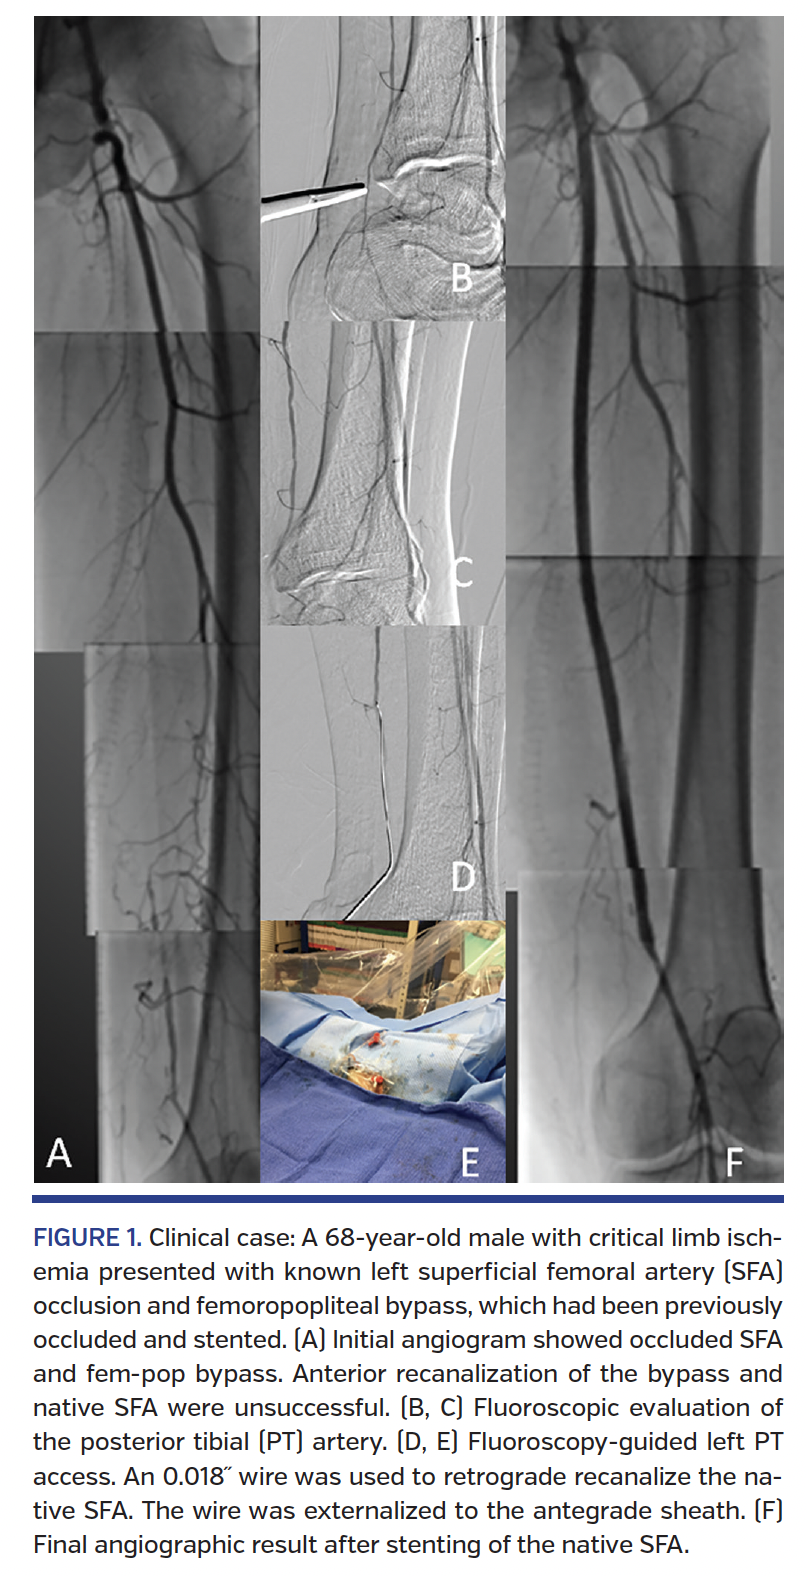

The PT is typically accessed behind the medial malleolus and the AT at the transition of the dorsalis pedis to the AT just above the instep of the foot. In those locations, the artery size can accommodate sheath entrance, the risk of compartment syndrome is minimal, and postprocedure hemostasis is easy (Figure 1). A 0.014˝ or 0.018˝ wire is advanced through the needle and a 4 Fr hydrophilic sheath is positioned. Nitroglycerin and verapamil are administered through the sheath and unfractionated heparin is given intravenously to achieve a therapeutic ACT >250 sec.